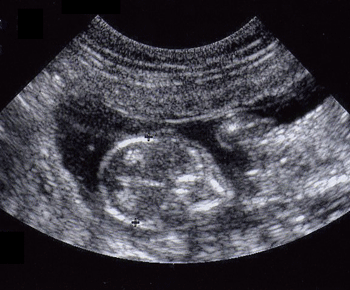

Echographie de gestation

Échographie de gestation

(Photo : © vetopsy.fr)